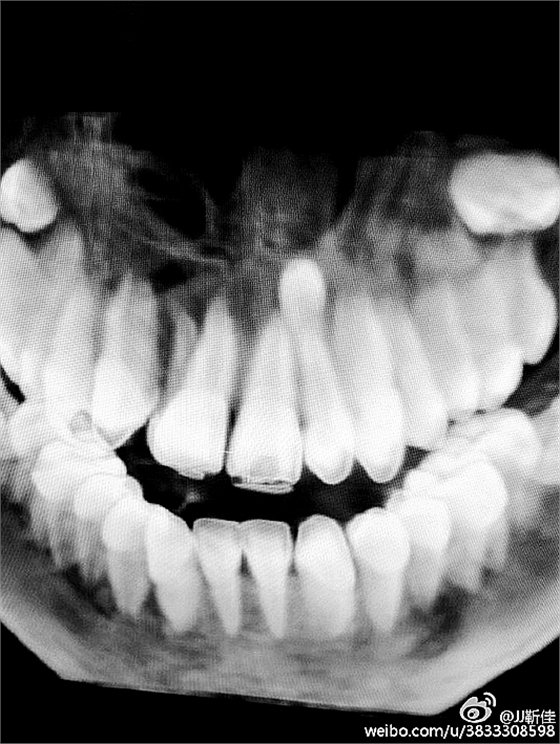

局部麻醉。

額外牙拔除

好大的額外牙

植入骨膏

覆蓋骨膜

縫合